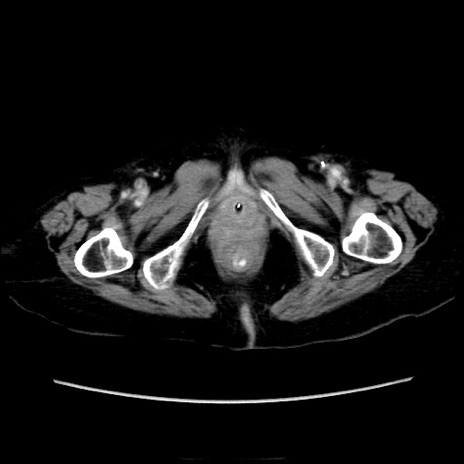

症例40(横断像)

【症例】90歳代女性

【主訴】腹痛・嘔吐

【現病歴】 食欲低下、嘔吐があり昨日他院受診。肺炎と診断され入院となる。入院後より腹部全体に圧痛あり。胃管留置され経過みていたが、症状持続するため、

当院転院となる。

【既往歴】胸椎圧迫骨折、胆石症

【身体所見】腹部:中央に激痛あり、圧痛あり、反跳痛不明

【データ】WBC 17100、CRP 18.82

横断像